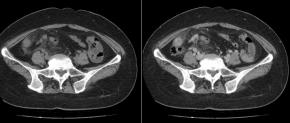

[Gastrointestinal [GI]] 40 Years/F, Right lower quadrant pain

Questions What is the most likely diagnosis?

Answer Epiploic appendagitis

Comments Epiploic appendagitis is a benign and self-limiting inflammatory condition involving an epiploic appendage. On ultrasound, it typically presents as a noncompressible, oval-shaped hyperechoic mass adjacent to the colon, often surrounded by a hypoechoic rim that reflects inflammation of the visceral peritoneum. Color Doppler imaging usually demonstrates absent or minimal internal vascularity within the lesion. The adjacent bowel wall is generally normal or only mildly reactive, which helps differentiate epiploic appendagitis from acute appendicitis or diverticulitis. Laboratory inflammatory markers are often normal or only mildly elevated. Accurate recognition of these characteristic ultrasound findings can obviate unnecessary surgical intervention, as conservative management is usually sufficient. Awareness of this entity is particularly important in the evaluation of patients presenting with acute abdominal pain.